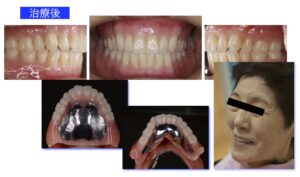

70代女性。今の入れ歯が動いて噛めないとの主訴で来院されました。10年前に現在使用中の上下顎総入れ歯を装着し、何回も調整を繰り返してきたとのこと。数年前から上下ともに入れ歯が動くのが気になるようになり、最近では入れ歯が何度もはずれるようになったため来院しました。うまく食事ができないため「よく食べれるようになりたい」、そして「入れ歯っぽくない自然な見た目」で製作して欲しいとのご要望がありました。

治療前 使用中の上下顎総入れ歯は、修理のつぎはぎ痕が多く存在しています。総入れ歯の土台となるあごの骨の吸収量が多く、また噛み合わせが左にズレていることから、入れ歯が吸着してよく噛めることがは難しい状態でした。

治療後 最初に治療用義歯を装着することにより、傷ついた土台の粘膜の改善と噛み合わせの正常化を図られたことから、最終義歯としてBPS義歯を装着しました。義歯の吸着は良好で、患者さんの生活の質(QOL)は向上し、大変満足いただけました。

治療用義歯の装着により「よく噛めるようになった」とのお話が聞け、入れ歯の土台となるあごの粘膜が健康になって、下顎左側偏位の修正が得られました。そこで最終義歯(BPS金属床義歯)を製作していくこととしました.製作ステップは治療用義歯製作と変わりません。見た目を綺麗にしたいとのご要望があり、歯肉の相当する部分をカラーリングして、より自然感のある美しい義歯に仕上げました。患者さんの笑顔も見られ、初診時に障害されていた生活の質(QOL)も70満点中14点と全ての項目で向上して、ご満足が得られました。